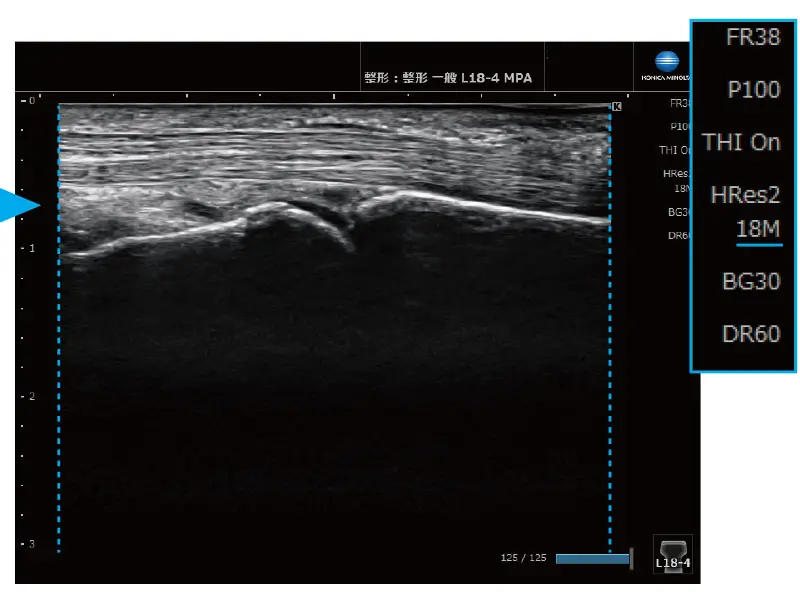

簡単操作で画像を最適化

MPA® 機能(Multi Parameter Adjuster)

表示深度を変更するだけで、あらかじめ設定した画質パラメーターが適用されます。例えば、表示深度を浅くすると高周波に、深くすると低周波や台形走査へ自動的に切り替わります。

≪深度:浅い≫ 台形走査OFF

≪深度:深い≫ 台形走査ON